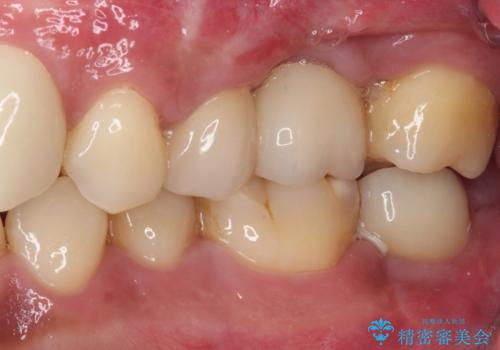

- ソーシャルメディアでのゲームに夢中になっている最中に車と接触し、前歯の抜歯を余儀なくされた患者様です。

初診時では前歯が保存できる可能性も模索しましたが、損傷が激しく3歯を抜去することとなりました。

保存となった隣在歯も神経が失活していており、補綴治療が必要であったので、オールセラミッククラウンにて補綴治療することとしました。

奥歯には元々欠損があり、欠損に伴う咬合不正も認められたため、部分矯正を行った上でインプラント補綴治療も行うこととしました。